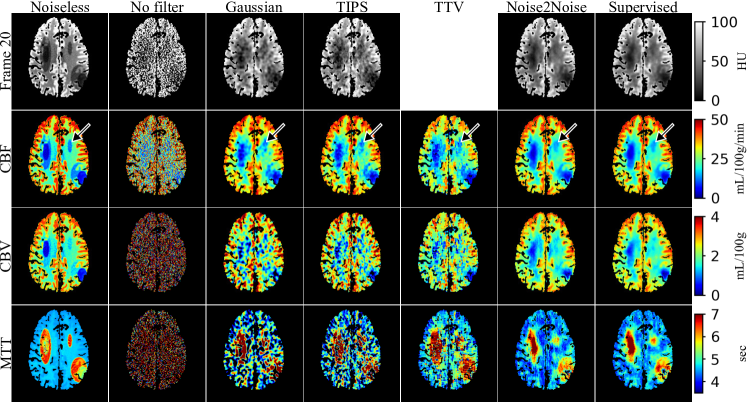

Refer to caption

Figure 7: Denoising results of a testing slice from the real dataset. The concentration maps at the 20th frame, CBF, CBV and MTT images are shown. A gray matter region is zoomed in for the CBF images to demonstrate the difference in spatial resolution. The time-concentration map is not given for TTV because it does not denoise the time frames. The ischemic core derived from the DWI image is shown as the green overlay on the time-frame images. It should be noted that in supervised learning, the network was trained on simulation images and applied to real images.

The denoising results of one testing slice are given in figure 7. Similar to the simulation results in figure 3, unfiltered parametric maps are almost unreadable and denoising was necessary. CBF images from Gaussian, TIPS, TTV and Noise2Noise demonstrated similar image quality to the simulation results at N0=2×105subscript𝑁02superscript105N_{0}=2\times 10^{5} in figure 3. In the zoomed-in gray matter areas of the CBF images, it could be observed that Noise2Noise had significantly improved spatial resolution compared to the other methods. Noise2Noise also had significantly reduced noise in CBV and MTT images compared to both Gaussian filter and TIPS. The TTV images had substantial blocky artifacts and structural bias of the gray matter compared to other methods.

The supervised learning results had a substantial blur of the gray matter compared to Noise2Noise, mainly due to the inconsistency between the simulation training data and the real testing data. The inconsistency also led to artifacts at the edge of cerebrum where the time-concentration maps, CBF and CBV had larger value.

Figure 8 shows the bias and std of ROIs inside normal white matter in denoised concentration maps. Noise2Noise had slightly larger bias compared to Gaussian and TIPS, but significantly lower bias compared to supervised learning. Most frames had bias less than 0.5 HU for Noise2Noise. Noise2Noise had the least noise level among all the methods. There was no result for TTV in figure 8 because it does not denoise the time frames.

Table II shows the mean contrasts, stds, and CNRs of the testing CBF maps which were calculated according to section V-C. Noise2Noise had similar contrast with Gaussian filter and TIPS and the least std among all the methods. Unfiltered CBF had lower contrast compared to Gaussian and TIPS because the max operator in the CBF calculation (17) led to non-zero-mean noise in the CBF images. Lower contrast was also observed for supervised learning results where bias was caused by inconsistent training and testing data. TTV had the best CNR because of the significantly larger contrast compared to the Gaussian filter and TIPS, which was mainly due to the overestimation of CBF of the reference white matter ROI. Noise2Noise had the best CNR among all the three methods (Gaussian, TIPS, Noise2Noise) without significant bias.